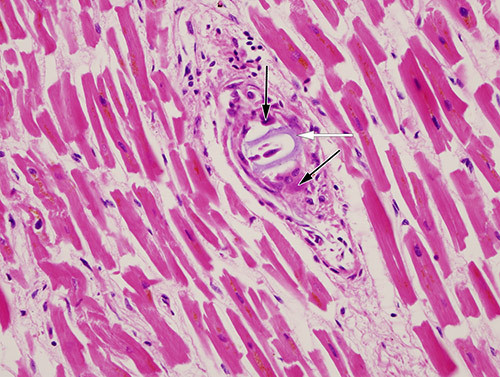

Ved mikroskopisk undersøkelse av hjertemuskulaturen fant man flere små intramurale arteriegrener okkludert av et basofilt fremmedlegememateriale slik pilen på bildet viser. I de fleste affiserte karene var det flerkjernede kjempeceller rundt materialet (svarte piler). I noen kar var det også en mer utbredt betennelsesreaksjon med lymfocytter og plasmaceller rundt de flerkjernede kjempecellene. Funnet passet med hydrofile polymergelemboluser (1, 2).